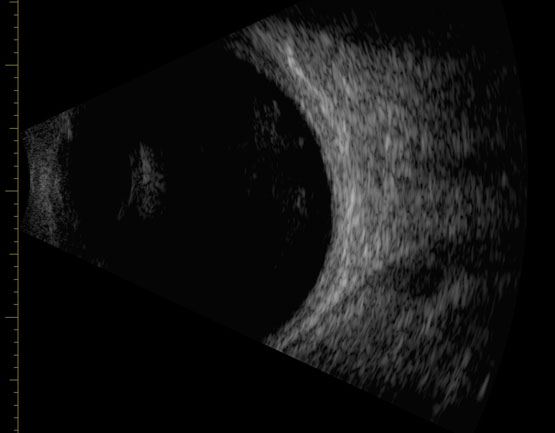

Ecografía ocular y ecobiometría

- Se realiza examen de ecografía ocular para evaluar enfermedades oculares en las que se incluyen tumores, disminución de la visión en la que no se puede observar por técnicas convencionales la retina.

- La ecobiometría se realiza para cálculos de lentes intraoculares en casos selectos.